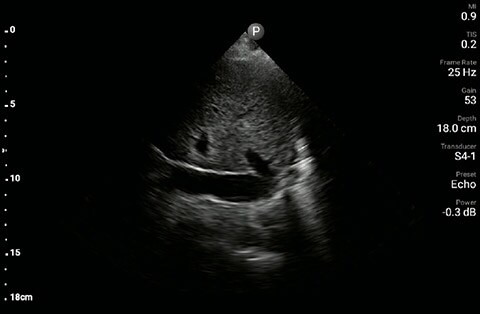

In this Lumify case study and summary video, Dr. Sara Nikravan discusses how she used her Philips Lumify handheld ultrasound system to guide the diagnosis and treatment of a patient experiencing shortness of breath.

POCUS with a small, extremely portable device had allowed for convenient and rapid evaluation, diagnosis, and intervention in a complex patient. A repeat chest X-ray just one hour after intubation showed marked improvement in the patient’s pulmonary edema.

Determining the cause of respiratory distress in the acutely ill can be challenging. POCUS with a three-point exam (F-TTE, IVC collapsibility, and lung ultrasound), as performed above, has been endorsed in this patient population as it can increase diagnostic accuracy in a timely fashion, especially as it pertains to acute decompensated heart failure.4 Furthermore, the use of a small portable device allows for convenience with rapid setup and use while minimizing the uptake of space. This becomes especially important when caring for patients that often have many providers attempting to provide care and initiate interventions at the same time, given the acute nature of their illness and potential for further rapid de-compensation.